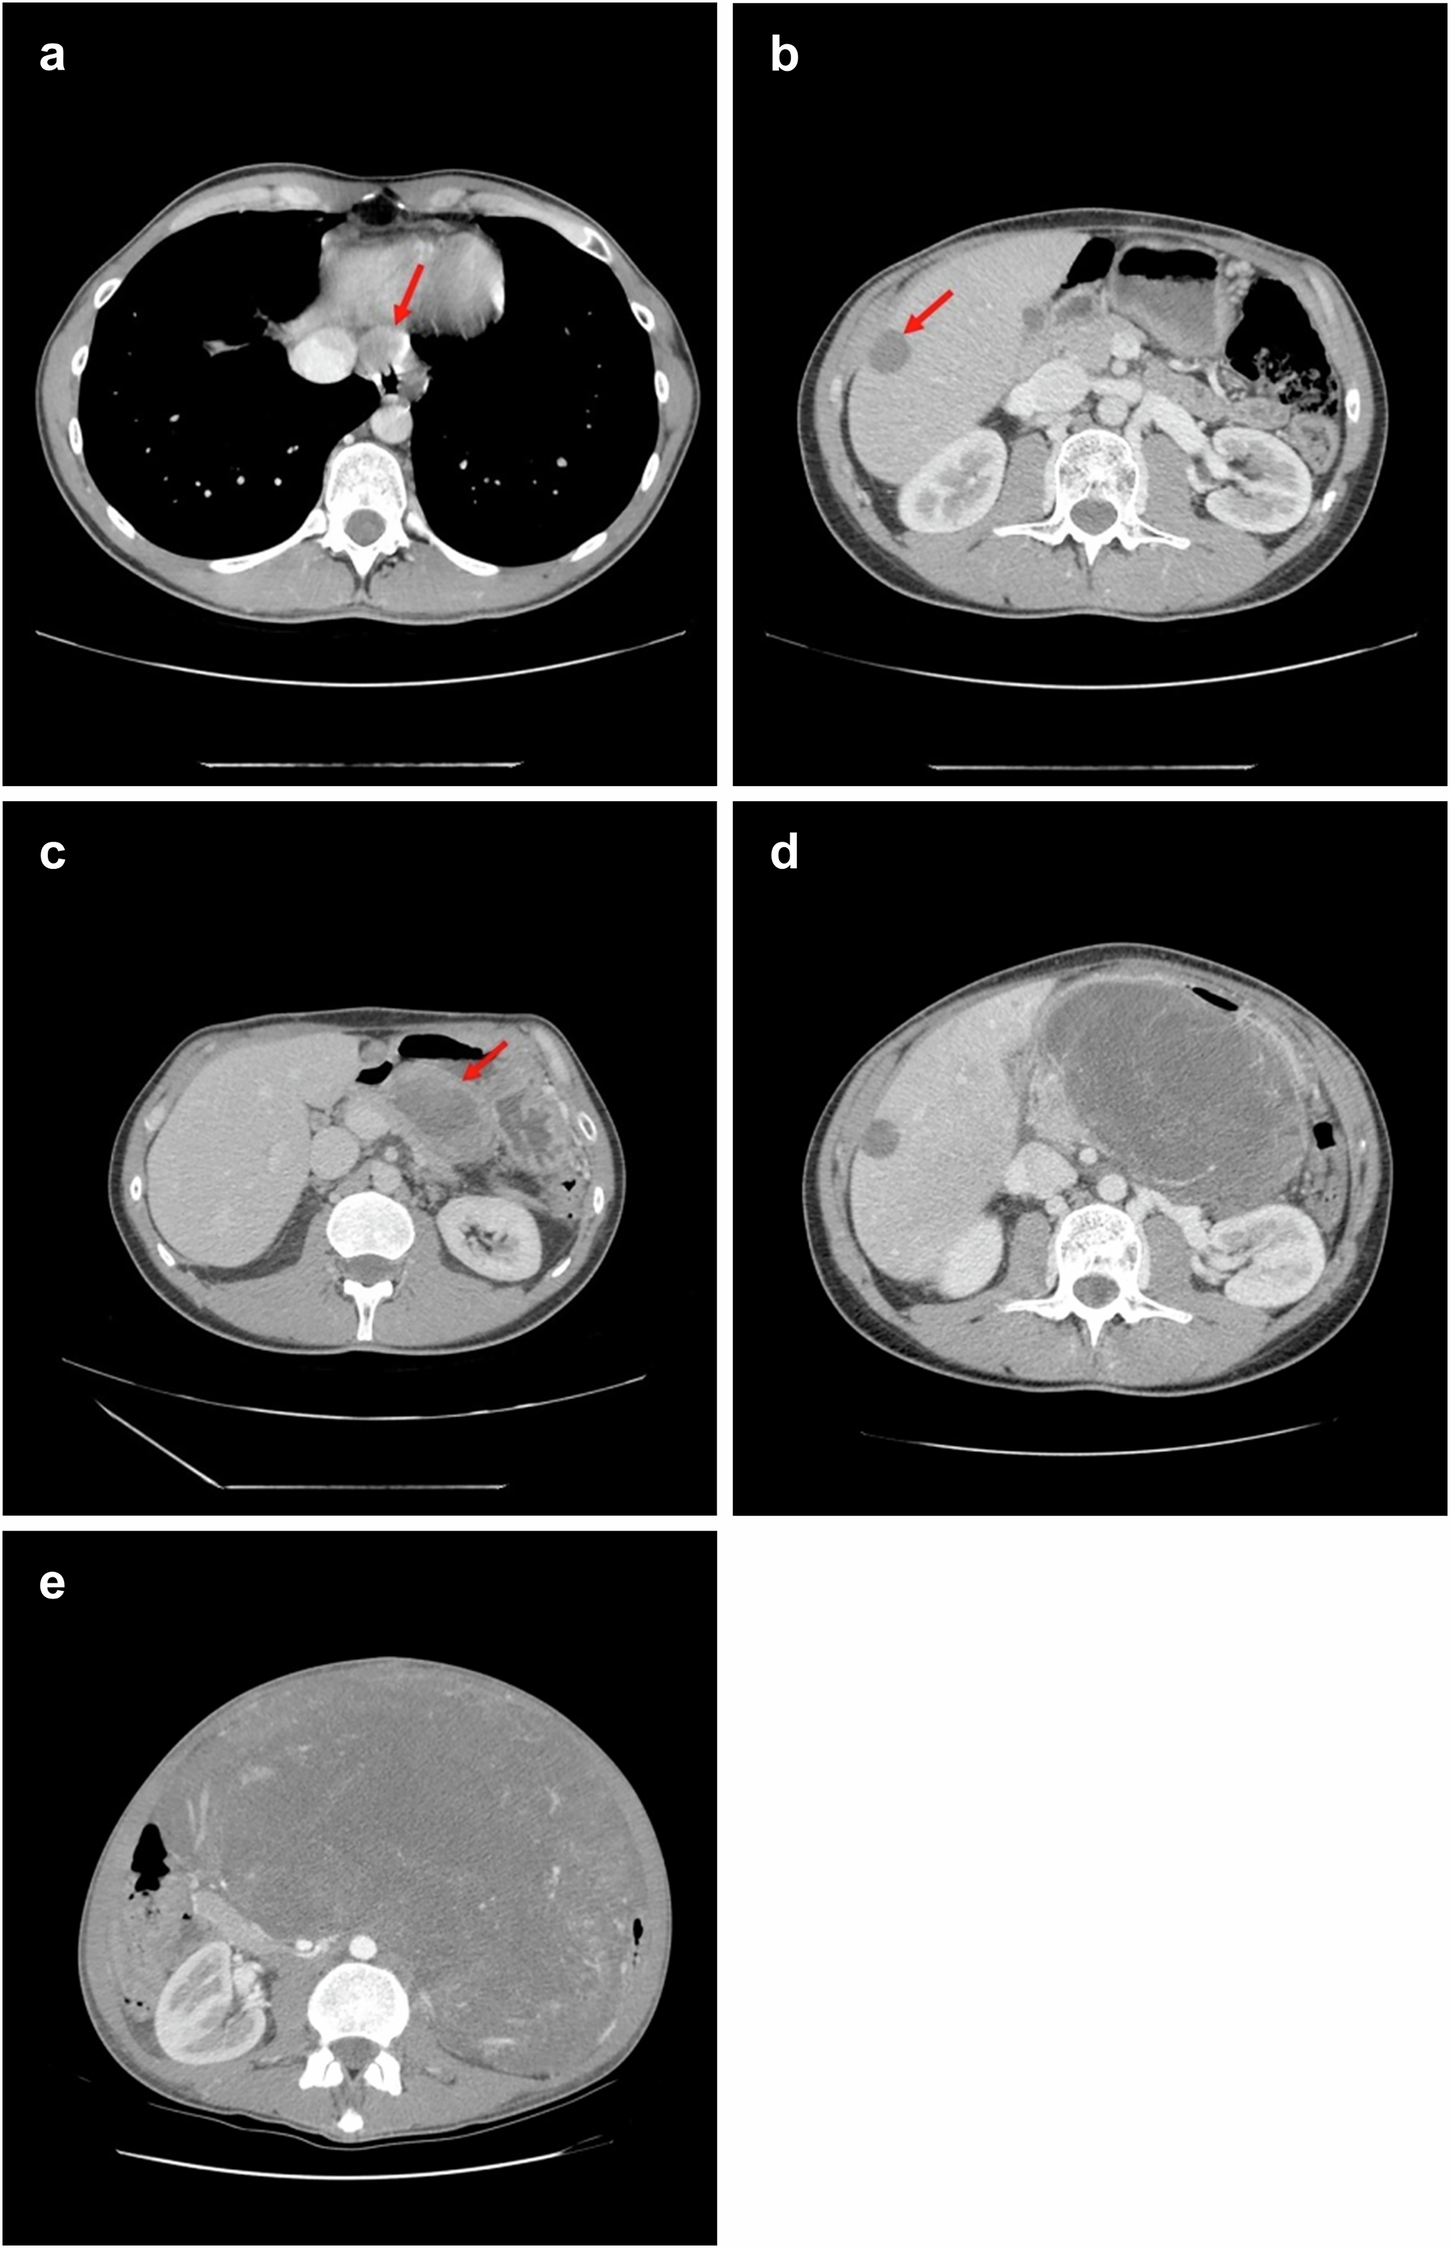

Fig. 2: CT imaging of the patient under treatment.

a, b Follow-up CT scan from September 2017 shows a partial response to imatinib, with reduced size of periesophageal and hepatic lesions (red arrows). c By February 2018, CT imaging reveals disease progression, with new intra-abdominal lesions, including an 8 cm perigastric mass with central necrosis (red arrow). d Following imatinib dose escalation, further progression is observed, including enlargement of the perigastric mass. e Imaging obtained at the late-stage of disease showing a large tumor mass occupying most of the abdominal cavity.